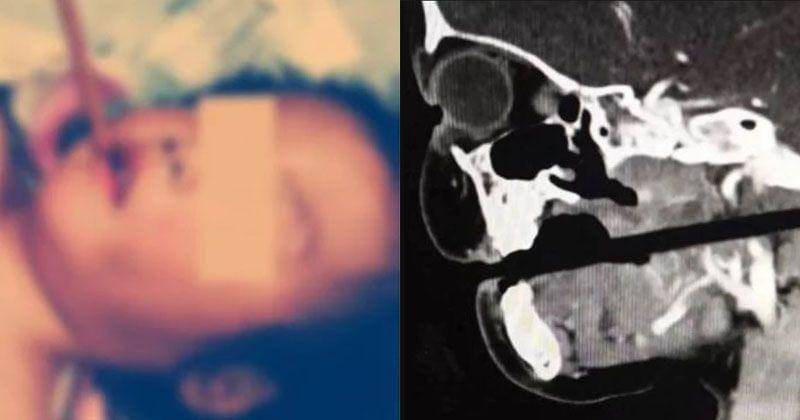

Nyatanya, hal tersebut telah terjadi pada seorang bocah berusia 3 tahun di Jiangxi, Cina, pada 11 April 2019 yang lalu.

Dilansir dari laman sg.style.yahoo.com, insiden tersebut bermula ketika si Anak diketahui sedang makan sambil berlarian memegang sumpitnya.

Malang, ia pun terjatuh dan kemudian sumpit yang dipegang tersebut menembus ke sisi mulutnya hingga menembus tengkorak.

Rupanya, sumpit tersebut telah masuk begitu dalam sampai ujung sumpit dapat dirasakan dari belakang lehernya.

Mengetahui hal tersebut, orangtuanya pun segera membawa sang Anak ke rumah sakit terdekat, yakni Rumah Sakit Xiangya Universitas Central South.

Setelah dilakukan CT scan, dokter mengungkapkan bahwa sumpit tersebut nyaris meleset menusuk bagian vital seperti batang otak, arteri karotid, dan vertebra leher. Bahkan sekitar 10 cm, sumpit tersebut telah masuk ke kepalanya.

Oleh karena itu, dokter kemudian memutuskan untuk melakukan operasi walaupun akan ada risiko yang terkait dengan pemberian anestesi.

Setelah dilakukan operasi, akhirnya sumpit pun berhasil dilepas, dan anak tersebut kini berada dalam kondisi stabil, meski masih tetap diamati.